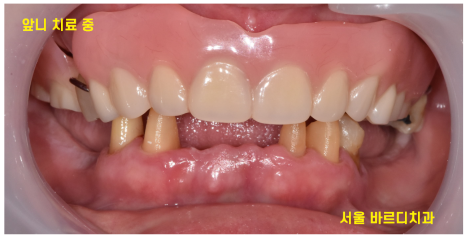

기다리시는 동안 치료할 수 있는 앞니부터 치료하였고요.

240430

13개의 임플란트 식립 후

전체적인 치아 치료 완료된 사진입니다.

맨 처음 상태가 기억나지 않을 정도이시죠~?